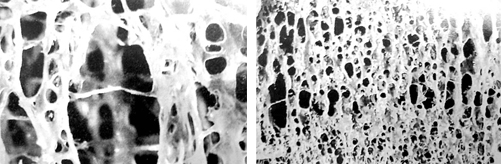

골다공증에 좋은 음식 10가지에 대해서 살펴보겠습니다. 골다공증은 뼈의 밀도가 감소되어서 쉽게 골절이 일어나는 질병이고요. 골다공증이 있다고 하면 관절 통증 및 보행에 괴로움을 느낄 수 있고요. 이러한 골다공증에 좋은 음식 10가지를 확인해 보시기 바랍니다!